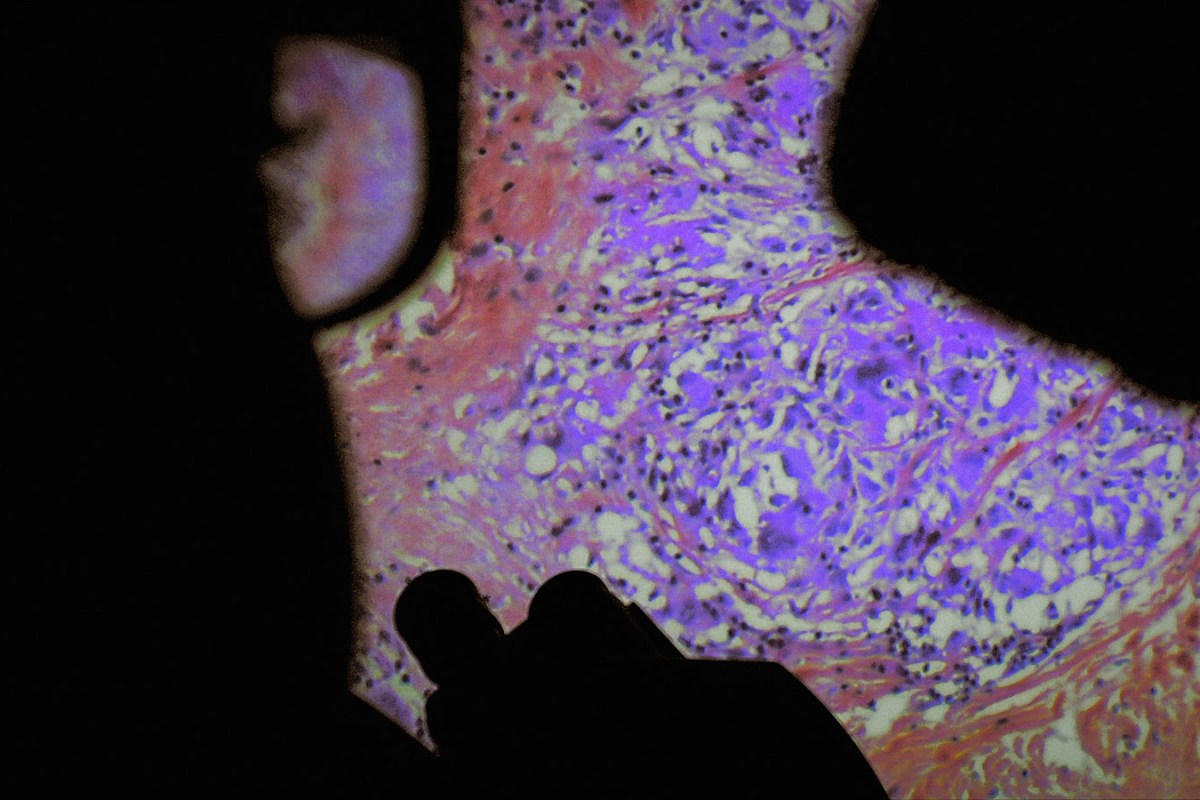

Au centre se trouvent, évidemment, le corps des individus en souffrance et ce qui s’y active, sous les effets des pathologies et des soins. Et c’est bien là que se passe l’essentiel du film, notamment en salles d’opération, avec d’emblée la question de cet acte très singulier qui fait qu’un être humain ouvre le corps d’un autre humain, et y introduit ses mains et des outils. Parmi ces outils se trouvent désormais très fréquemment des appareils de prise de vues, qui produisent des images particulières, destinées à permettre de soigner.

Il et elle ont aussi fait construire une caméra spécialement conçue pour s’approcher au plus près des opérations en cours, sans les perturber. Mais surtout, les cinéastes se sont mis d’accord avec les médecins et avec les patients pour avoir également accès aux images filmées à l’intérieur des corps pour les besoins des interventions.

D’une diversité et d’une précision jamais approchée, en tout cas pour une diffusion autre que spécialisée, ces images ont surtout cette vertu qui est elle absolument inédite de connecter par un sidérant travail de montage les images filmées par les réalisateurs et celles enregistrées par les machines. Ce travail, qui organise les images et les sons, les rythmes et les déplacements, est au sens propre un travail poétique, une composition pour percevoir autrement, sentir autrement, penser autrement. (…)